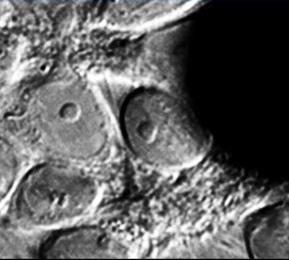

Machine Learning in Neuroscience

- Hamid R Rabiee

- Ali Ghazizadeh

- Mackenzie W Mathis

- Reza Lashgari